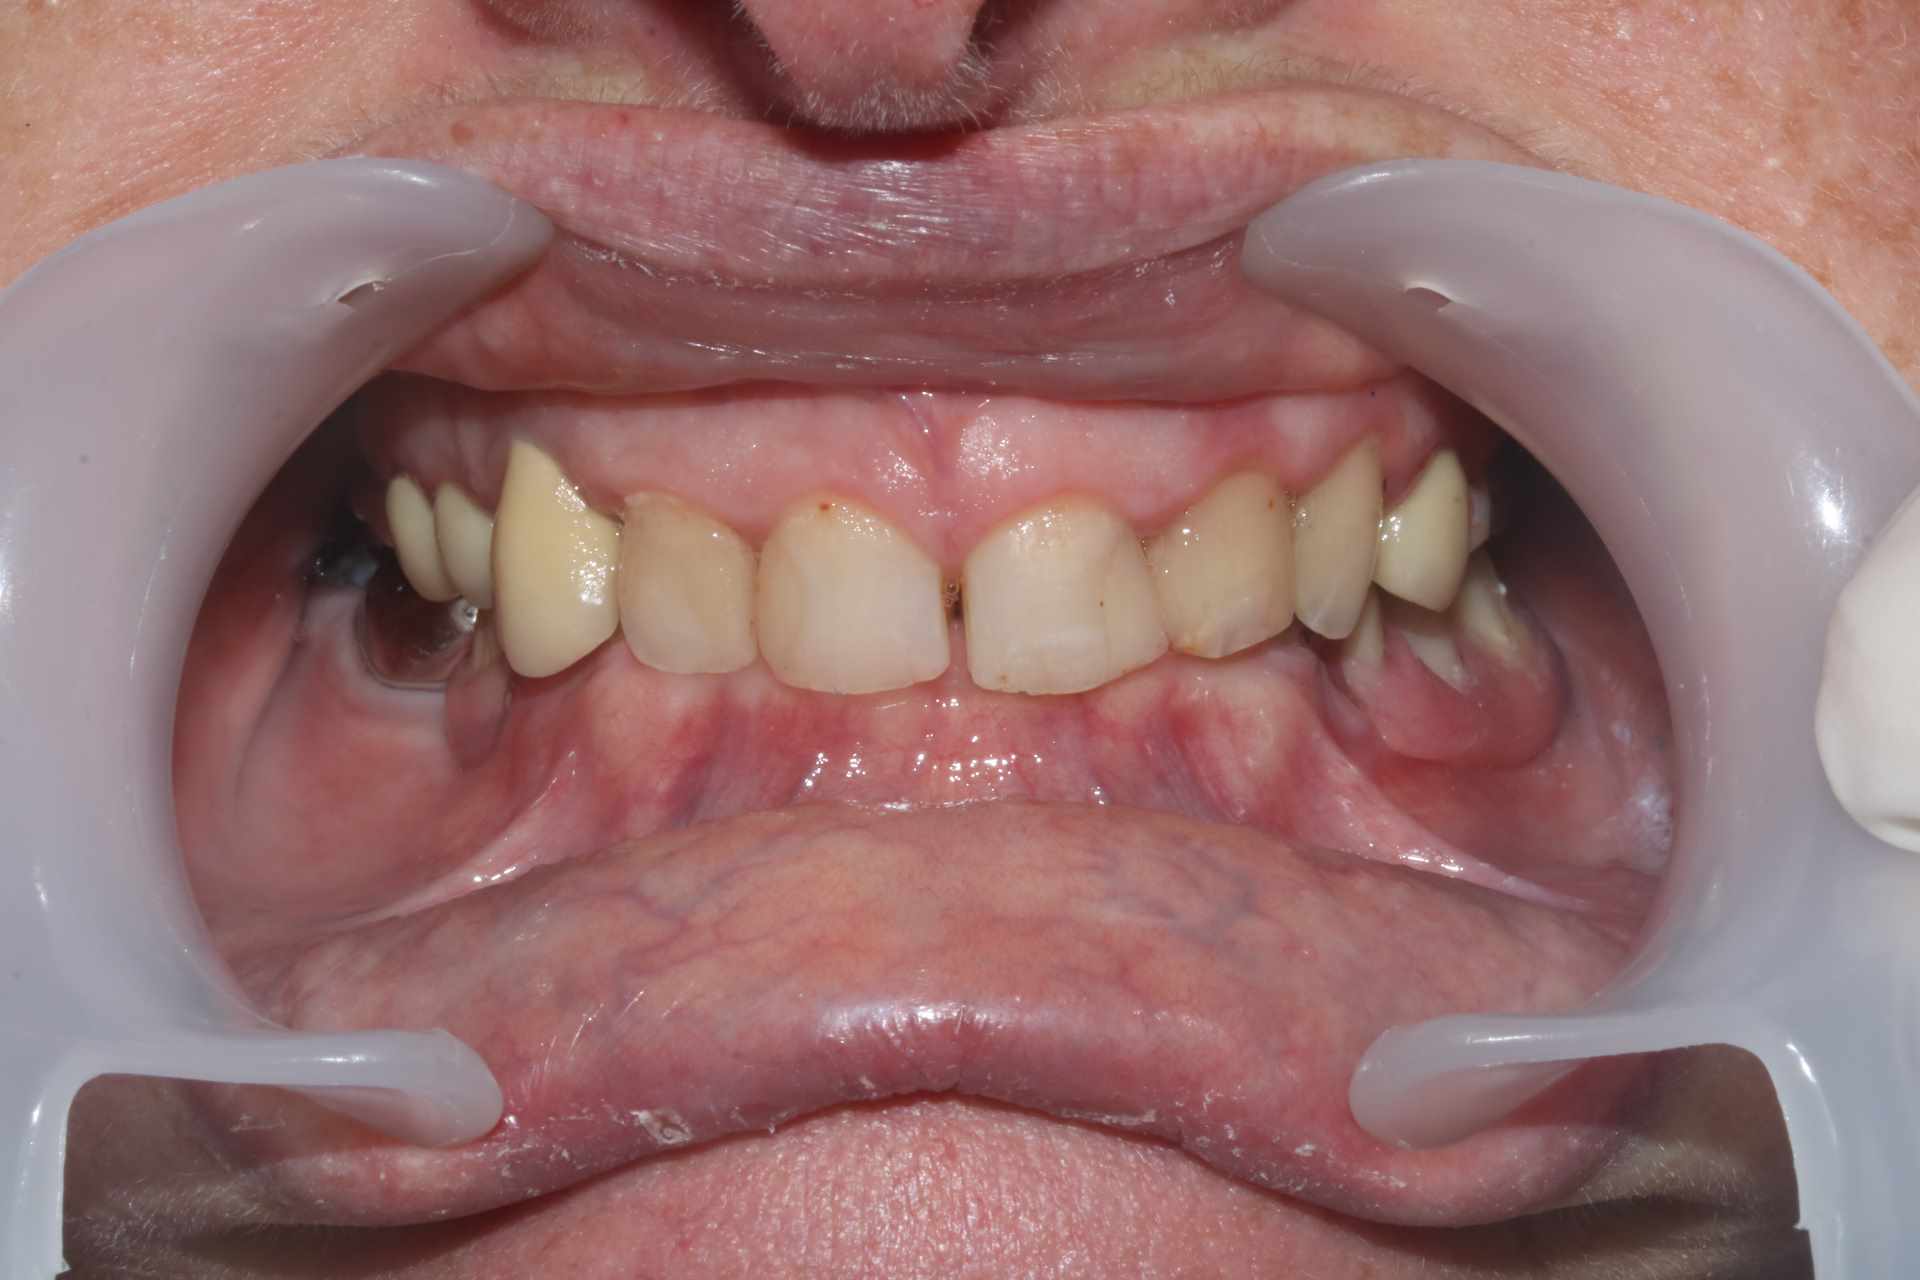

La patiente venait pour 34 35 descellées et 13 mobile. J'en suis encore au stade on traite les urgences avant de s'attaquer vraiment au cas. Vous voulez pas me donner un coup de main ? je ne sais pas trop par ou commencer !

On a une classe 2 2 majeure. ultra verrouillée. Je ne vois pas comment m'en sortir sans augmenter la DV qui a été malmenée par les soins et couronnes diverses a peu près tous en sous occ à mon avis sauf la 13 qui a explosé.

Je ne suis pas certain qu’il y ait eu tant de perte de DV. Ce serait à vérifier avec d’anciennes photos ou panos.

Je dis ça parce qu’ on constate quand même peu d’usure sur les dents encore saines et elle a une fameuse supra-alvéolie maxillaire.

Oui la couronne sur sur 13 c'est une honte, volumineuse et beaucoup trop longue. Je suspecte une couronne faite avec un mordu unilatéral pour expliquer une telle aberration.